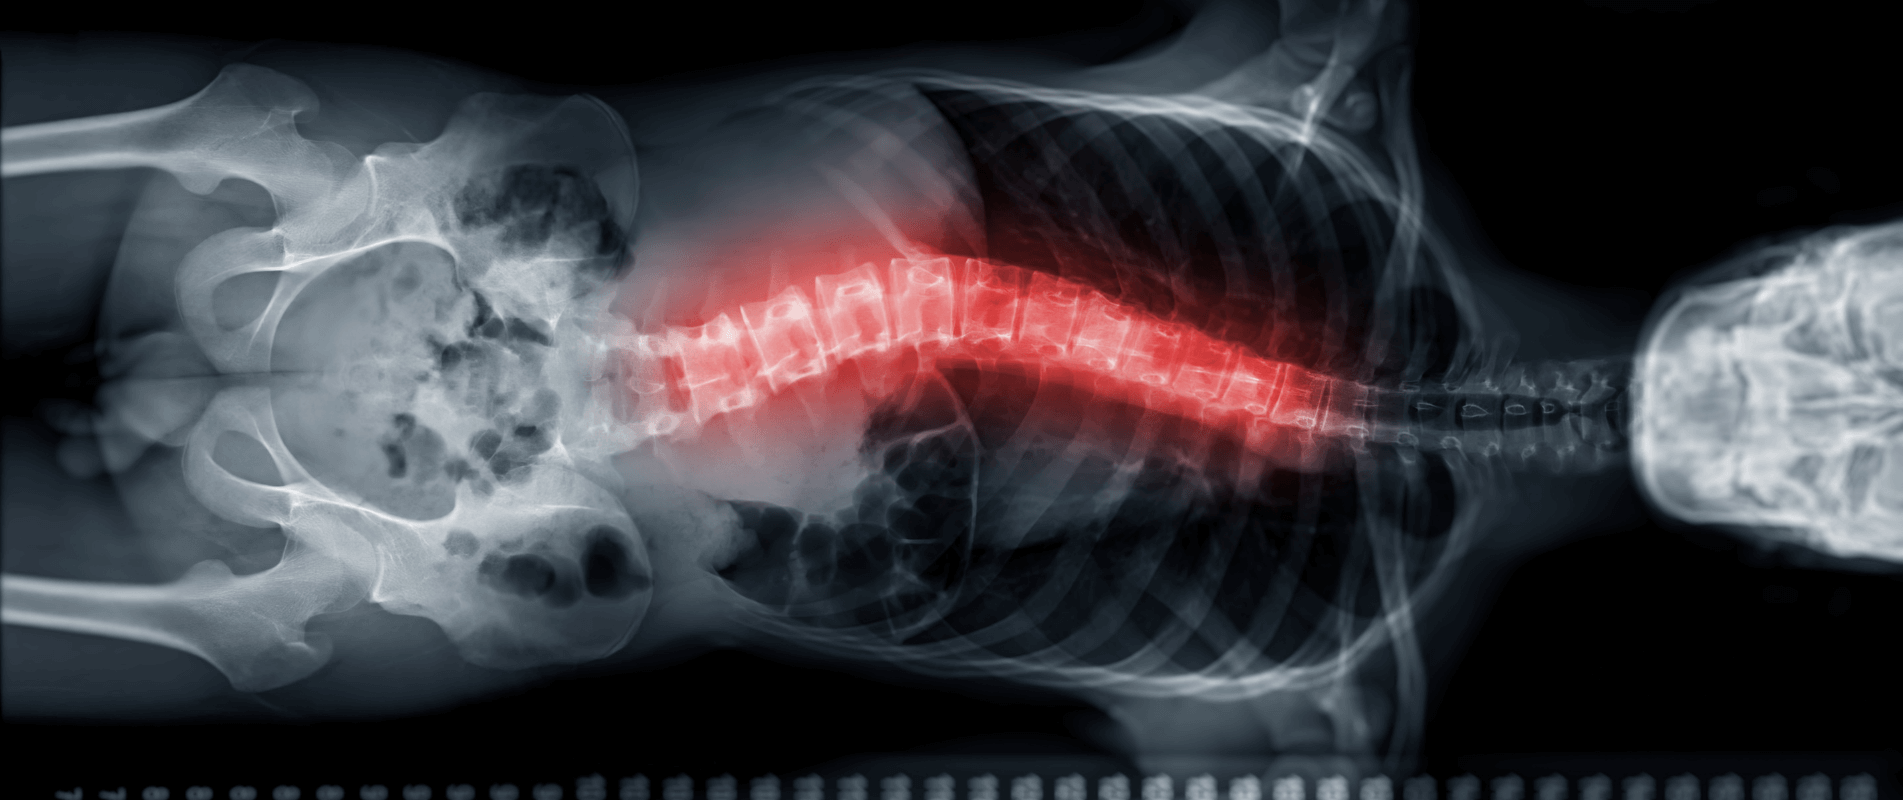

Scolioza idiopatică este o deformare a coloanei vertebrale care apare fără o cauză cunoscută. Aceasta înseamnă că o porțiune a coloanei se curbează lateral și se rotește ușor, modificând postura și aspectul spatelui. Se definește printr-o curbură de cel puțin 10 grade, observată pe radiografie. Apare cel mai frecvent în perioada adolescenței, în timpul creșterii rapide, și nu este cauzată de o boală, un accident sau o problemă congenitală.

Ce este unghiul Cobb?

Unghiul Cobb este standardul medical de evaluare a severității scoliozei. Acesta se măsoară pe imaginea radiologică, trasând linii paralele cu vertebra cea mai înclinată de sus și cea mai înclinată de jos din zona afectată. (așa cum este reprezentat în imaginea alăturată).